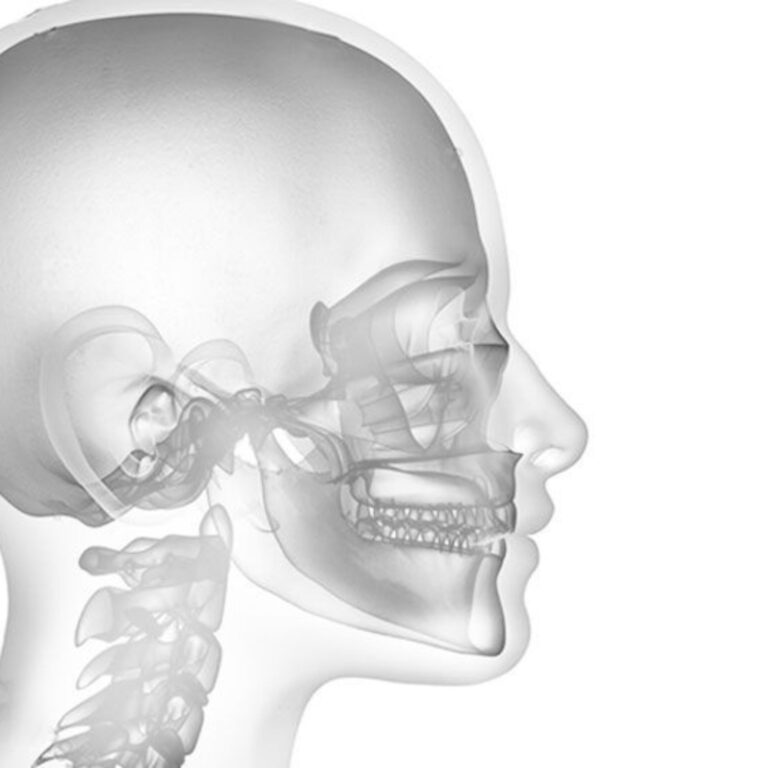

La chirurgie orthodontique, aussi appelée chirurgie orthognathique, est envisagée lorsque des désalignements dentaires et maxillaires ne peuvent être corrigés uniquement avec des appareils orthodontiques. Ces interventions sont souvent recommandées pour améliorer la fonctionnalité, l’esthétique du visage, et la qualité de vie.

- Ostéotomie mandibulaire : Réalignement de la mâchoire inférieure.

- Ostéotomie maxillaire : Réalignement de la mâchoire supérieure.

Chirurgie de réduction ou augmentation osseuse

- Correction des anomalies de la forme et de la taille des mâchoires.